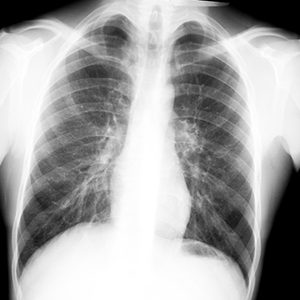

Для того, чтобы не допустить развития запущенных форм туберкулеза, в нашей стране все взрослые и подростки 15 лет и старше 1 раз в 2 года обязательно проходят флюорографию или рентгенологическое обследование легких.

Диагностика Для выявления заболевания кроме пробы Манту проводят флюорографическое обследование (ФЛГ) органов дыхания, которое позволяет обнаружить ранние стадии туберкулеза легких. Этот метод диагностики совершенно безвреден при одно — двукратном исследовании в течение года, доза рентгеновского облучения очень мала.